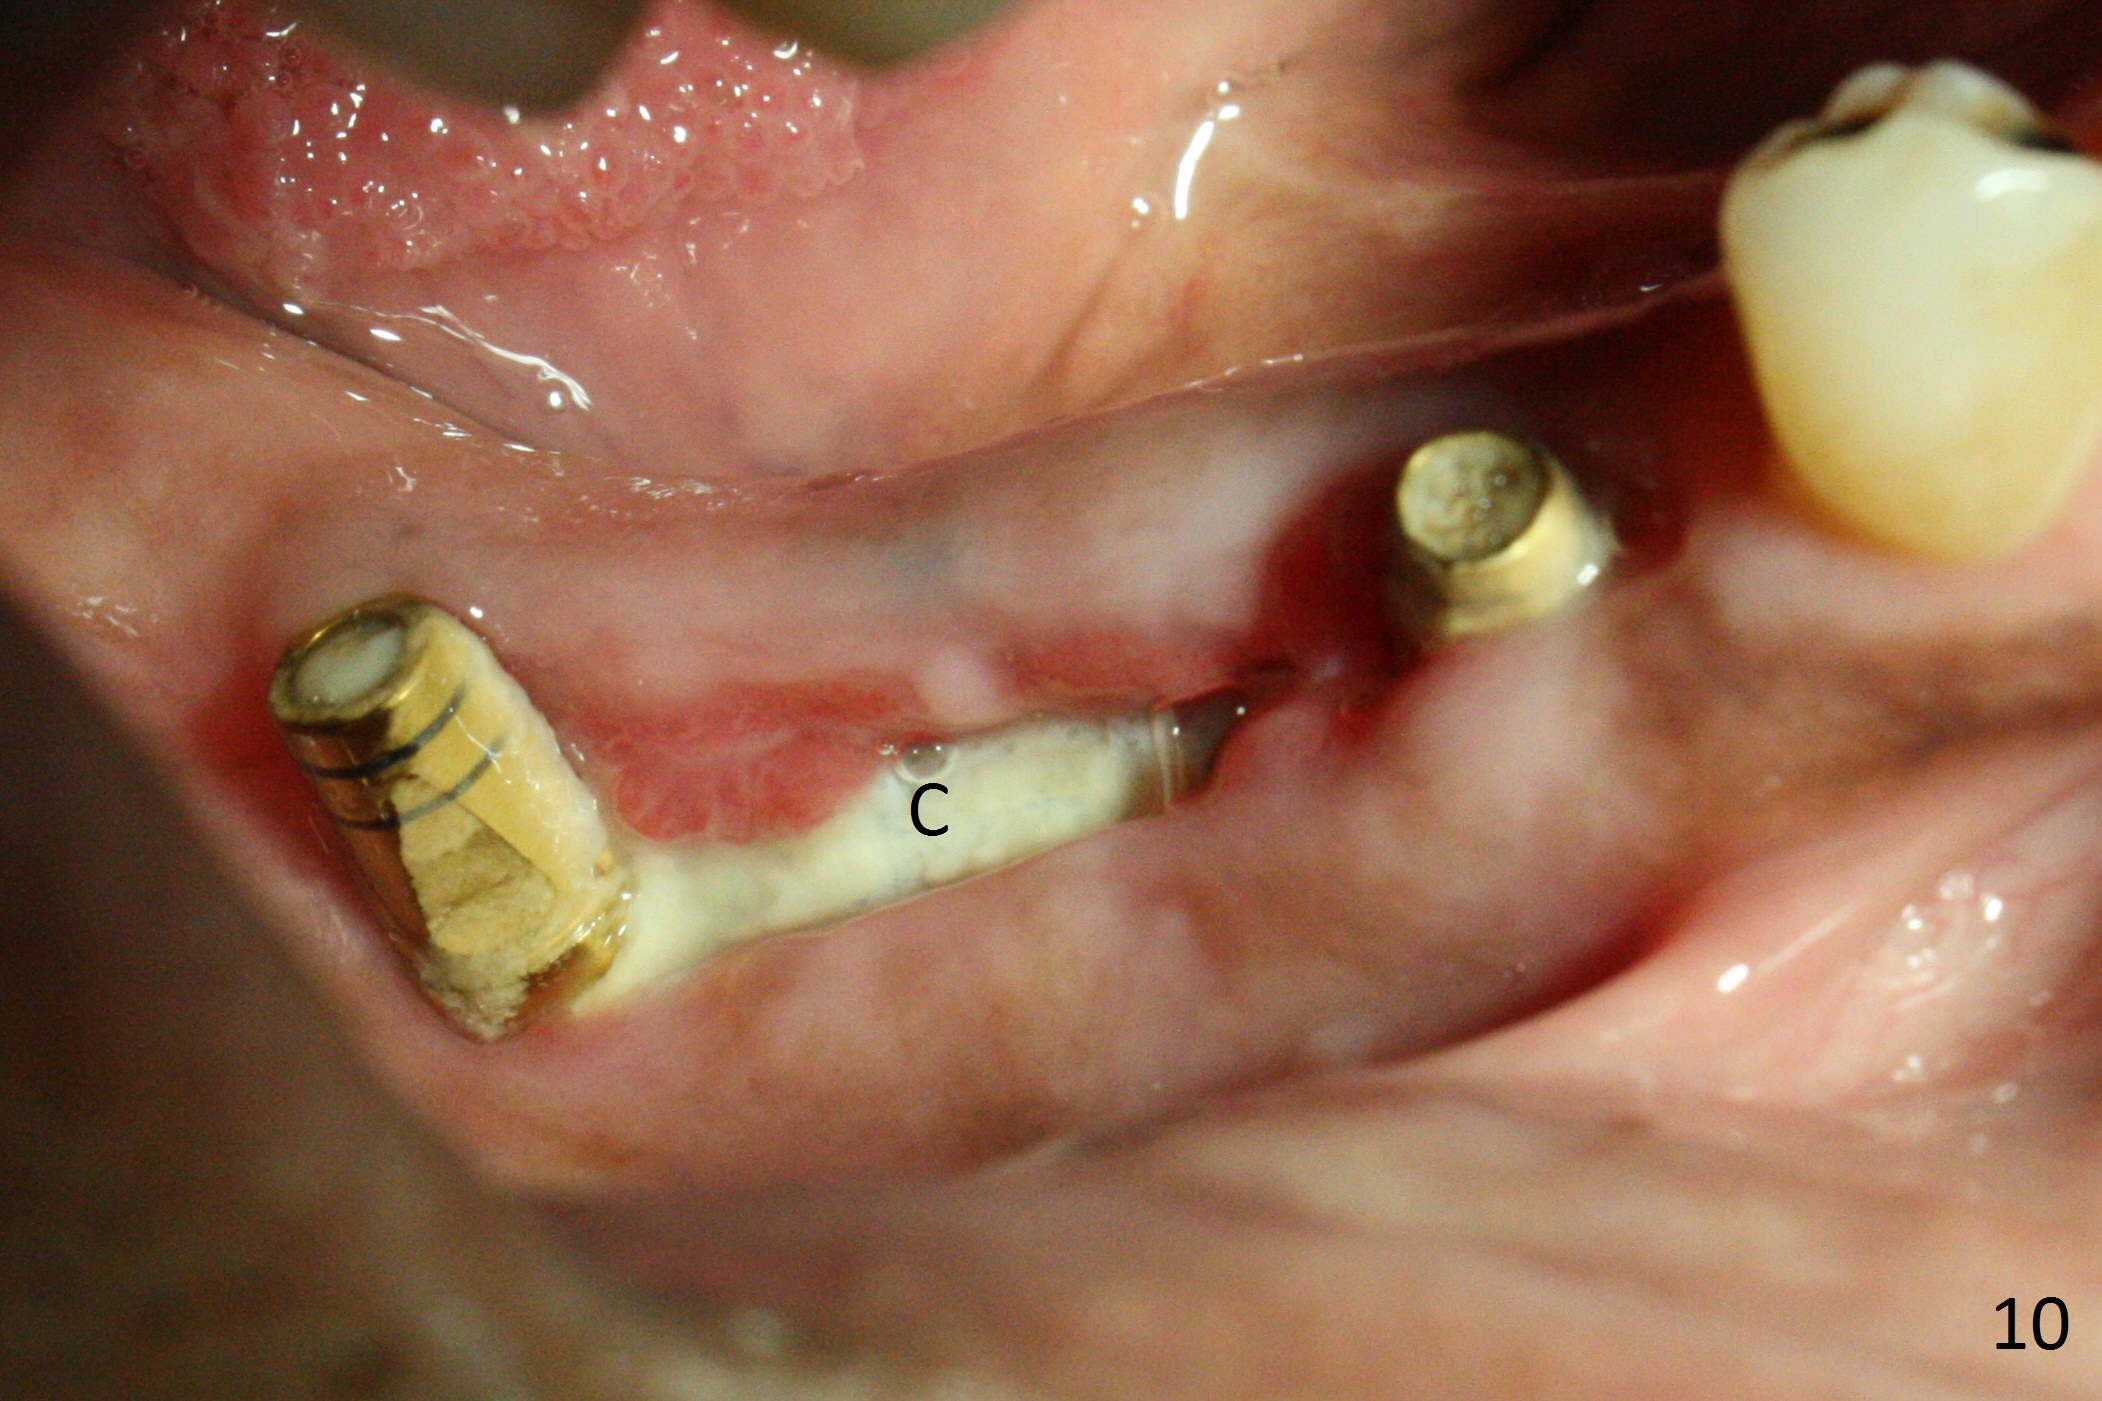

The patient is doing fine postop. He returns asymptomatic 5 weeks postop. There is minimal gingival erythema lingual to the non-resorbable membrane (Fig.10 C). After removal of plaque around the abutments, the membrane is removed (Fig.11). Two weeks later, the wound has healed (Fig.12). The abutment at #29 is basically buried, while the one at #31 is covered by the lingual gingiva.